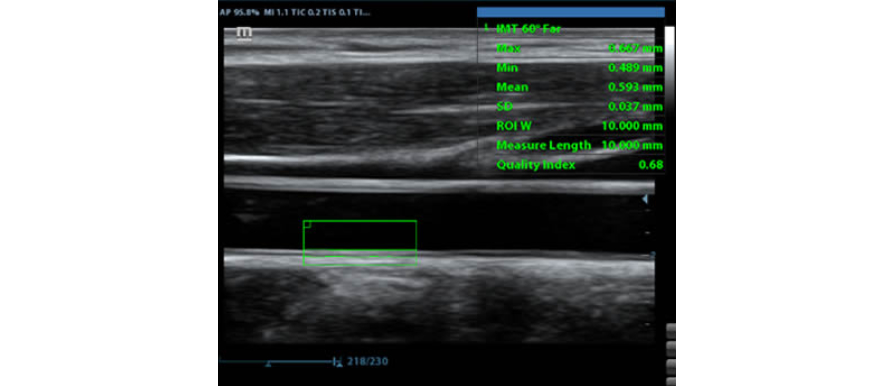

MediciÃģn automÃĄtica del grosor de la pared anterior y posterior, lo que proporciona un indicador preciso del estado de la carÃģtida.